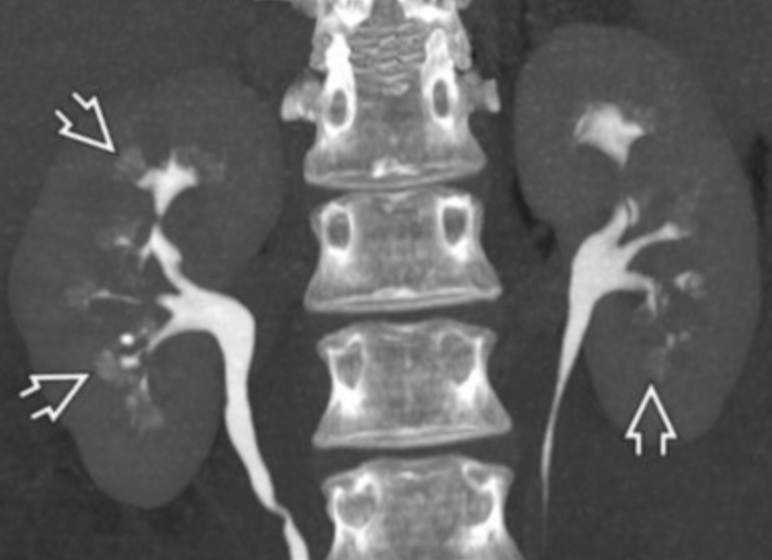

• Maiden waist sign - medial deviation of the middle 1/3 of both ureters

Retroperitoneal Fibrosis

• Literally fibrotic changes in the retroperitoneum typically for unknown cause/trigger although can be related to radiation, drugs, malignancy or pretty much anything else but vast majority of cases are idiopathic

• Fibrotic changes results in compression of ureters and vasculature -

• If there is displacement of the Aorta, IVC there should be concern for malignant etiology

• Classically there should be encasement but no invasion of these structures